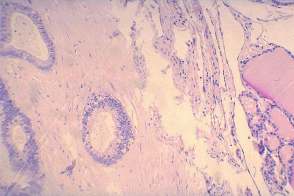

Histopathology: metastasis of a colon cancer to the thyroid.

• The less obvious failure was my cytological diagnosis. Knowing the final diagnosis, of course, I would say otherwise. And re-examining the cytology sample later helped to avoid a similar mistake. Although the cytological picture resembles that seen in papillary cancer, the cytological pattern should raise colonic cancer. The clue is the palisading arrangement of tumor cells.